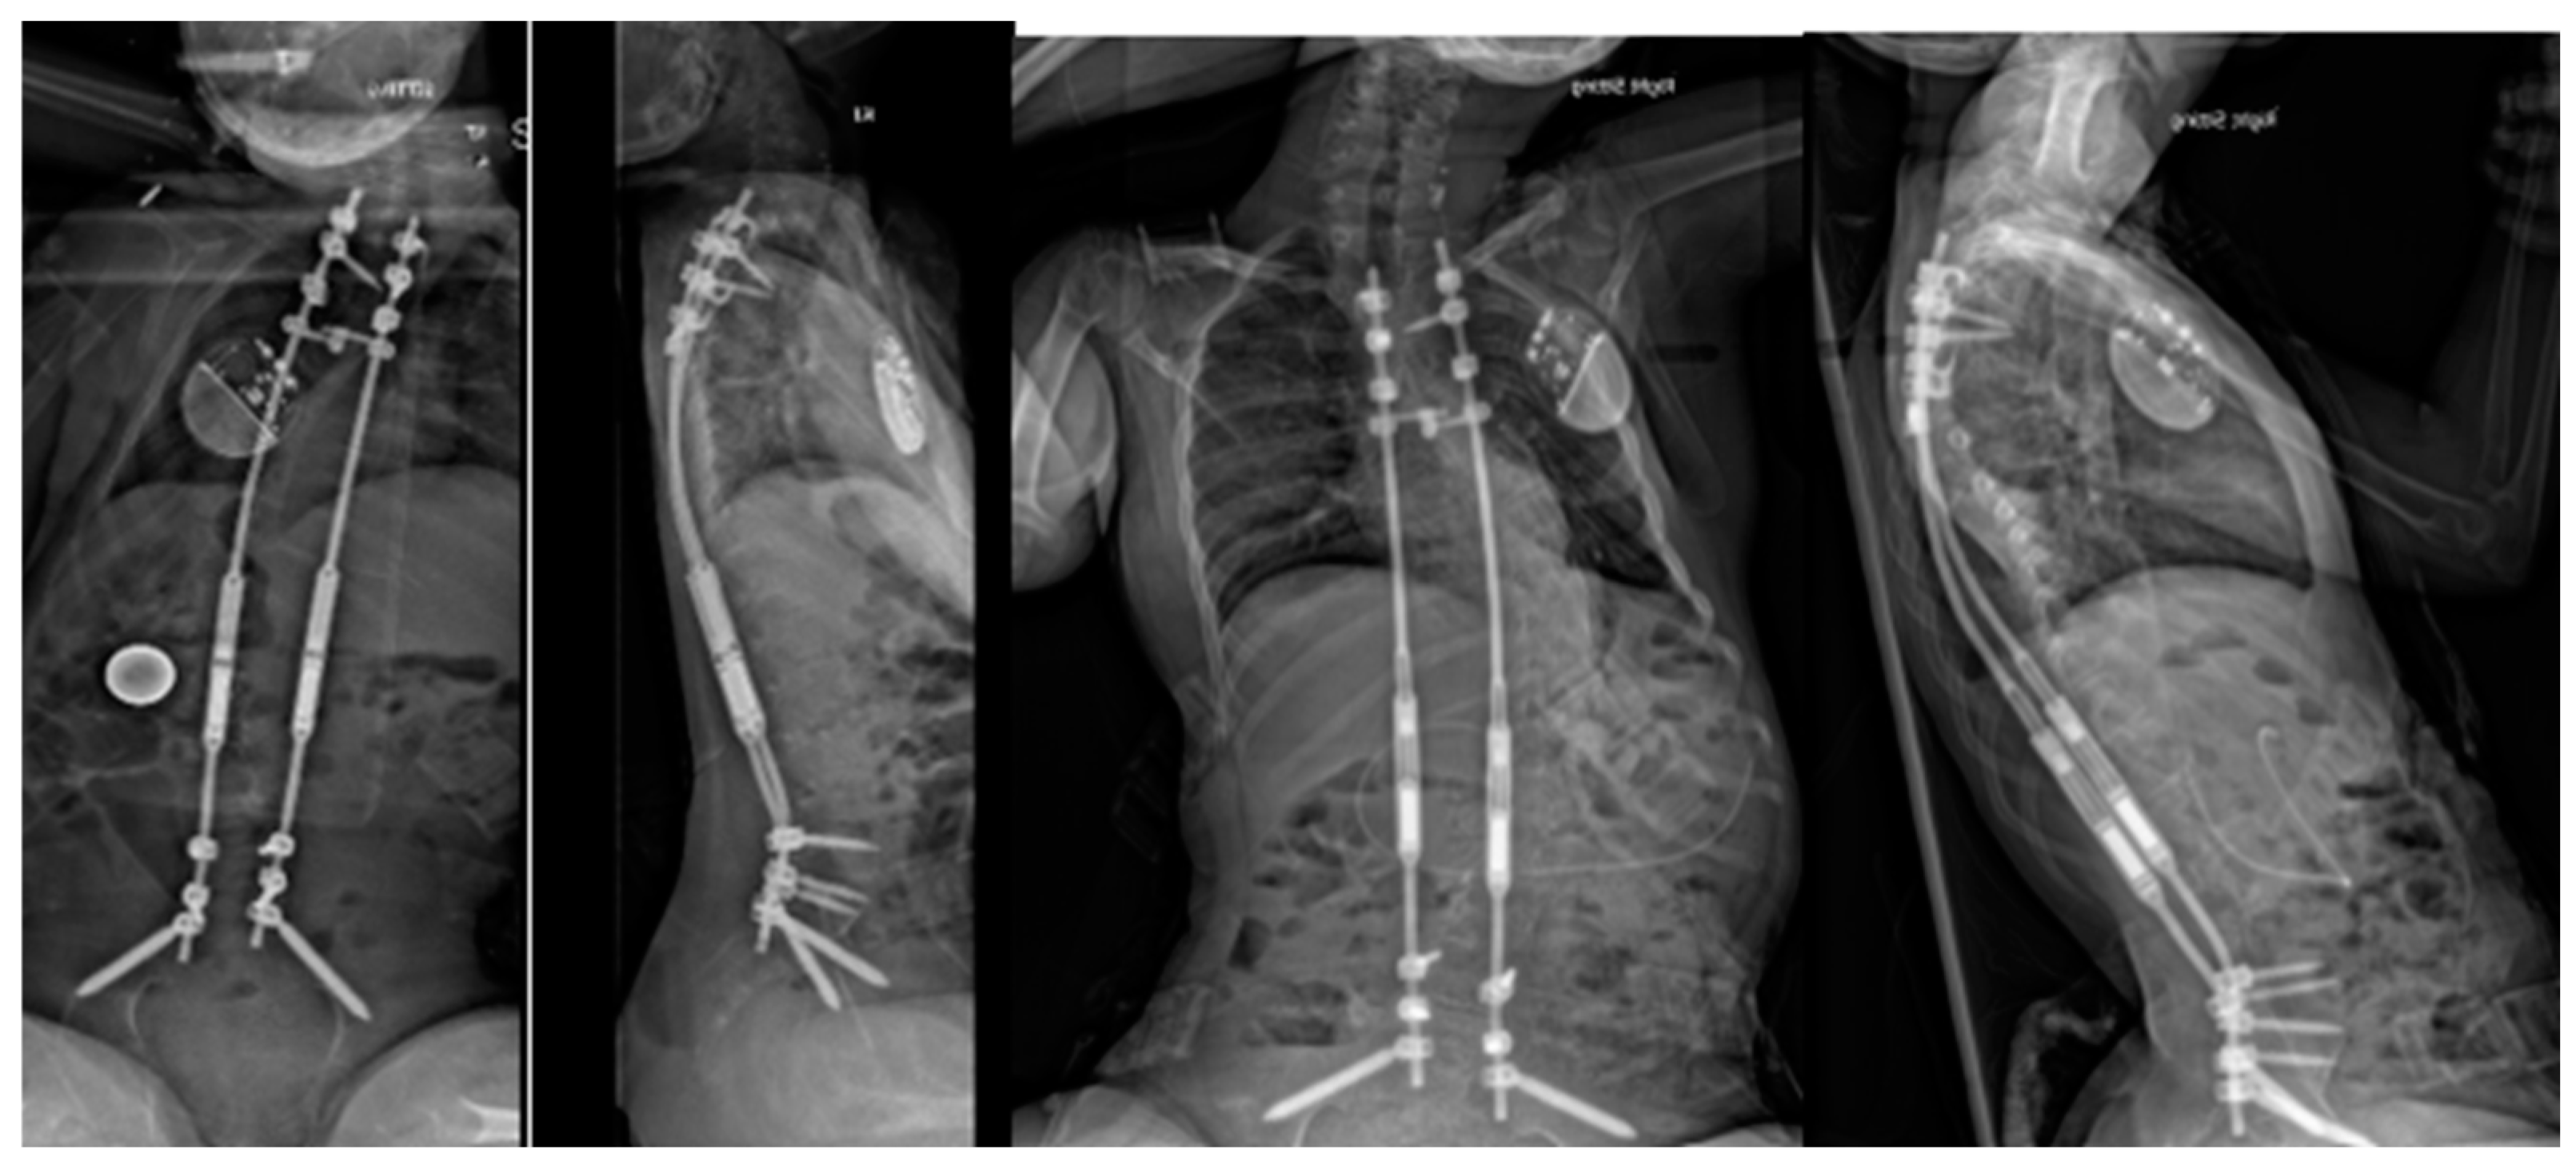

6. Distraction-Based Methods

- Skaggs, D.L.; Akbarnia, B.A.; Flynn, J.M.; Myung, K.S.; Sponseller, P.D.; Vitale, M.G.; Chest Wall and Spine Deformity Study Group; Growing Spine Study Group; Pediatric Orthopaedic Society of North America; Scoliosis Research Society Growing Spine Study Committee. A classification of growth friendly spine implants. J. Pediatr. Orthop. 2014, 34, 260–274. [Google Scholar] [CrossRef]

- Akbarnia, B.A.; Breakwell, L.M.; Marks, D.S.; McCarthy, R.E.; Thompson, A.G.; Canale, S.K.; Kostial, P.N.; Tambe, A.; Asher, M.A.; Growing Spine Study Group. Dual growing rod technique followed for three to eleven years until final fusion: The effect of frequency of lengthening. Spine 2008, 33, 984–990. [Google Scholar] [CrossRef] [PubMed]

- Thompson, G.H.; Akbarnia, B.A.; Kostial, P.; Poe-Kochert, C.; Armstrong, D.G.; Roh, J.; Lowe, R.; Asher, M.A.; Marks, D.S. Comparison of single and dual growing rod techniques followed through definitive surgery: A preliminary study. Spine 2005, 30, 2039–2044. [Google Scholar] [CrossRef] [PubMed]